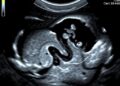

The evolution of stem cell research has ushered in a new frontier in developmental biology, particularly through the advent of stem cell-based embryo models (SCBEMs). These innovative constructs leverage the unique capabilities of pluripotent stem cells, enabling scientists to replicate the early stages of embryo development. By creating SCBEMs, researchers aim to glean insights into human development and the underlying mechanisms of various diseases, thereby paving the way for futuristic therapeutic advancements. However, the unfurling potential of SCBEMs brings forth a host of ethical and regulatory challenges, drawing mixed responses from governments and stakeholders across the globe.

Australia has emerged as one of the few countries to actively address the ethical implications of SCBEMs by classifying blastocyst-like structures similarly to traditional embryos. This regulatory stance ensures that these structures are granted the same ethical considerations afforded to embryos, reflecting a recognition of their potential to contribute to significant scientific breakthroughs. This regulatory equivalence underscores the need for a thorough understanding of the moral status of these novel biological entities, which is crucial for balancing scientific innovation with ethical responsibilities.

An essential proposal arising from this analysis suggests that SCBEMs should be distinctly categorized apart from fertilized embryos. By doing so, researchers can sidestep some of the stringent limitations placed on embryo research while establishing clear ethical guidelines that consider the unique characteristics of SCBEMs. This differentiation can provide researchers with the necessary latitude to explore innovative research avenues while maintaining a responsible ethical standpoint.